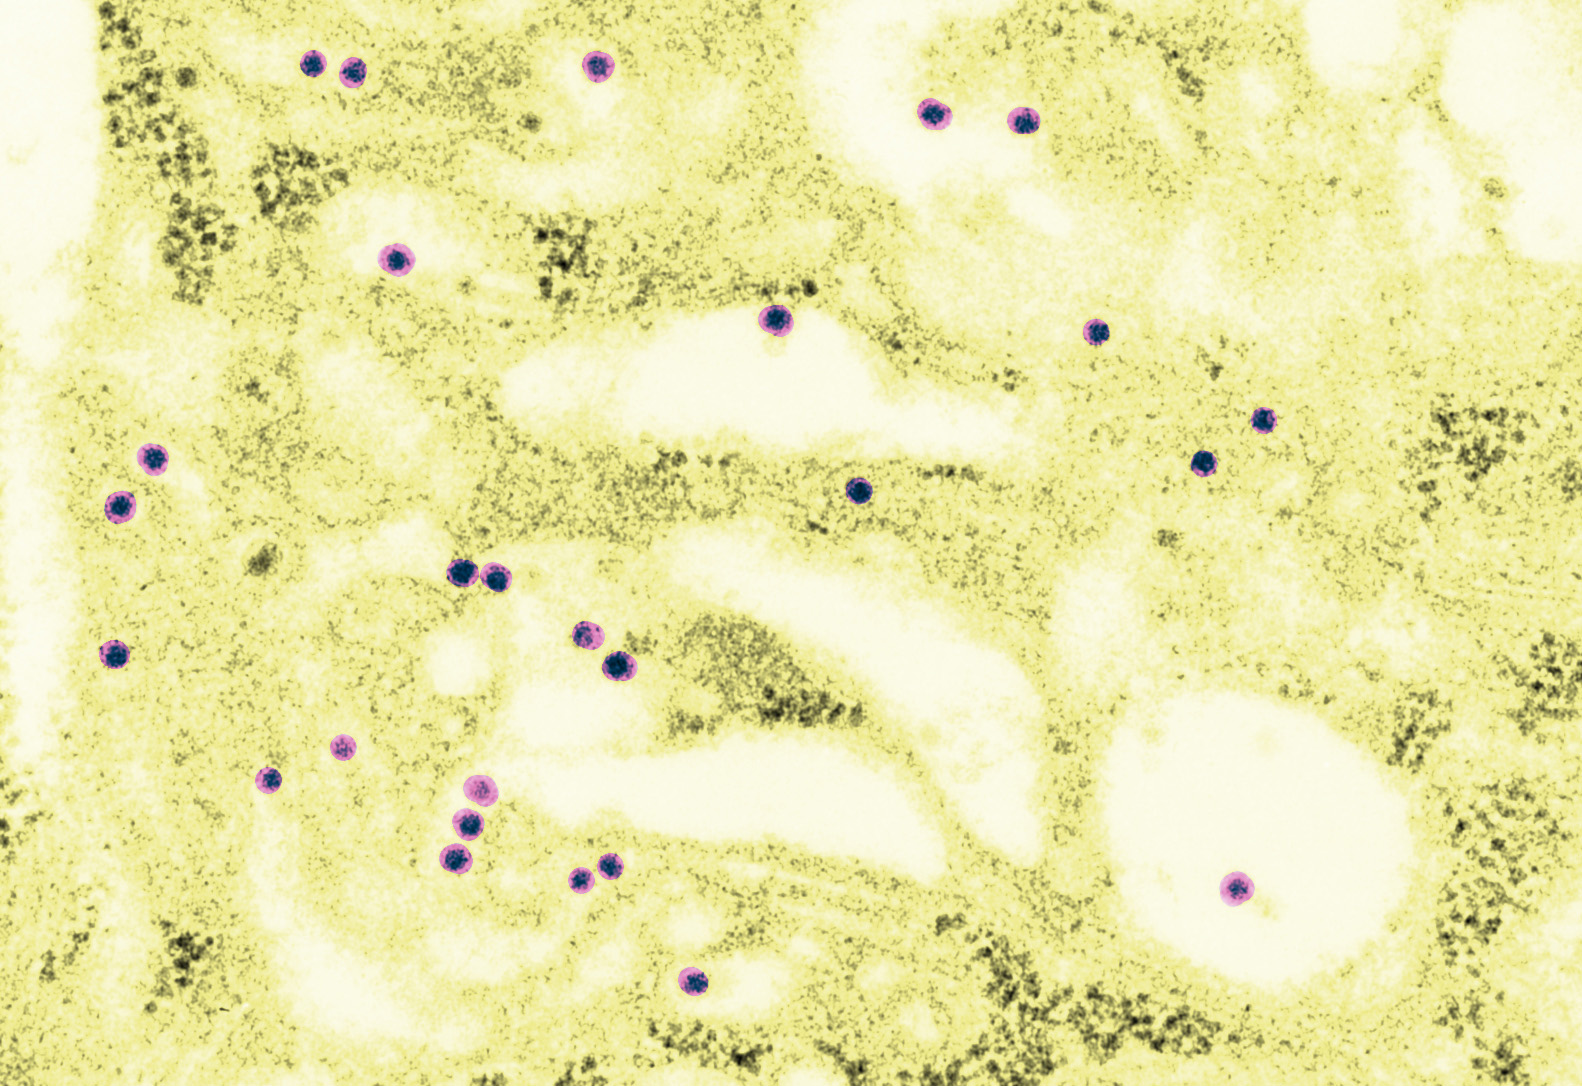

Image colorisée, le virion est en vert.

Images : copyright Institut Pasteur